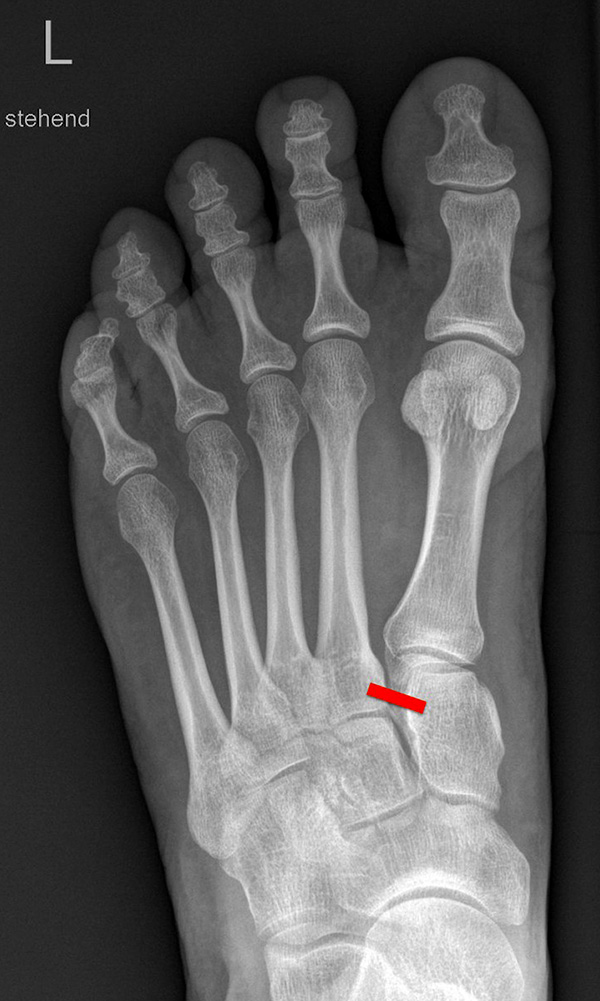

Auf den dp-Aufnahmen sollte der mediale Rand der Metatarsale-2-Basis mit dem medialen Rand des Os cuneiforme intermedium eine homogene Linie ohne Stufenbildung bilden (Abb. 7+8). Außerdem ist auf den Abstand zwischen der Metatarsale-1- und -2-Basis zu achten. Dieser sollte nicht größer als 2 mm bzw. im Vergleich zur Gegenseite nicht mehr als 1 mm erweitert sein. In bis zu 90% der Fälle zeigt sich ein sogenanntes „Fleck sign“ (Abb. 9), ein knöchernes Fragment zwischen der Metararsale-1- und -2-Basis im Sinne eines knöchernen Ausrisses des Lisfranc-Ligaments an der Metatarsale-2-Basis 211936410. Oft liegen zusätzliche Frakturen der Metatarsalebasen oder der Tarsale vor, die ebenfalls identifiziert werden sollten. Bei jeder Mittelfußbasisfraktur sollte umgekehrt an eine Lisfranc-Verletzung gedacht werden.

Zum Lesen der Bildbeschreibung und zur Vollansicht bitte die Bilder anklicken.

In der Schrägaufnahme sollte der mediale Rand des Cuboids mit dem medialen Rand der Metatarsale-4-Basis eine homogene Linie bilden.

In der seitlichen Aufnahme ist auf Dislokationen und Subluxationen in den Tarsometatarsalgelenken sowie auf einen Verlust des Fußlängsgewölbes zu achten. Bei Instabilitäten des 1. Strahls bzw. Abflachung des Fußlängsgewölbes tritt in der Seitaufnahme die plantare Kontur des Os cuneiforme mediale tiefer im Vergleich zur Basis des Metatarsale 5. Darüber hinaus sollte die Cyma-Linie im Bereich des Chopartgelenkes in der Seitaufnahme eine harmonische S-förmige Linie bilden.